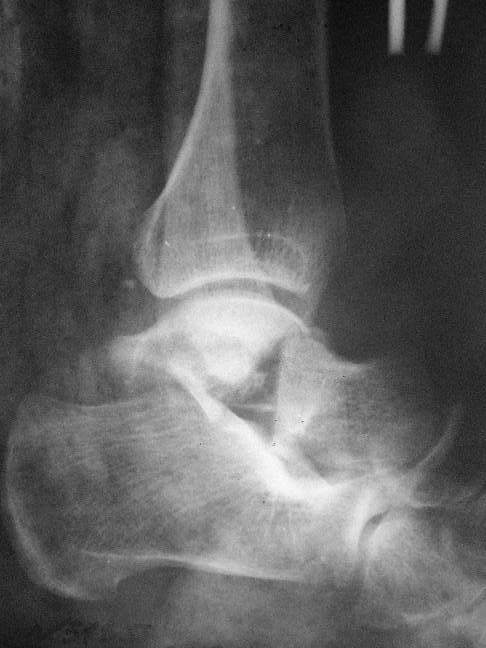

Прошу коллег помочь советом.3 дня назад поступила пациентка 23 года с переломом шейки ладьевидной справа, переломом лодыжек и заднего края б/берцовой кости со смещением и подвывихом кзади, переломом внутреннего мыщелка правого бедра без смещения. Дежурными хирургами проведена репозиция в левом г/ст суставе успешная, попытка репозиции таранной кости ухудшило положение отломков. Планируем провести повторную репозицию и фиксацию винтами. 1. Закрытая репозиция рентгенконтоль интраоперационный (аппарат Арман) ификсация из заднее-наружного доступа. 2. При неудачной закрытой репозиции переходим на открытое вправление двумя доступами медиальным и латеральным "по ходу оси таранной кости" и через дополнительный задний доступ вводим винты кортикальные 4,5 мм или 3,5 мм 3. после открытой репозиции фиксация двумя винтами через боковые доступы погружая их под суставную поверхность Сергей Зырянов ЦРБ Новосибирская область

Переломовывих тарана с повреждением медиальной стороны. Через 4 часа после поступления проведена репозиция и фиксация тарана после Irrigation&Debridment. Частичное несращение медиальной лодыжки не беспокоит, вернулся к активному образу жизни. Полная нагрузка разрешена через 11 недель. Финальные снимки через 11 месяцев.